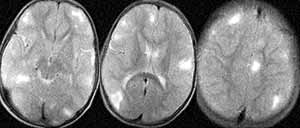

Больной К. 9 лет. Жалобы на наличие миоклонических судорожных припадков, задержку психоречевого развития. Кожа бледно-розовая, на лице, руках — туберозные бугорки. Печень +2 см, селезенка не пальпируется; в правой половине живота определяется образование. По данным РКТ головного мозга обнаружены субэпендимальные кальцинаты с четкими контурами и признаки внутренней гидроцефалии (Рис. 1). При проведении РКТ и УЗИ почек визуализируются двусторонние солидные опухоли размером до 82х90х126мм. (ангиомиолипома — по данным гистологического исследования). (Данные исследования предоставлены Республиканским научно-исследовательским цетром детской онкологии и гематологии; РК-томограф Tomoscan SR (Philips).

[Увеличить]

Рис. 1. РК-томограммы головного мозга. Визуализируются мультифокальные очаги высокой плотности, расположенные субэпиндимально.